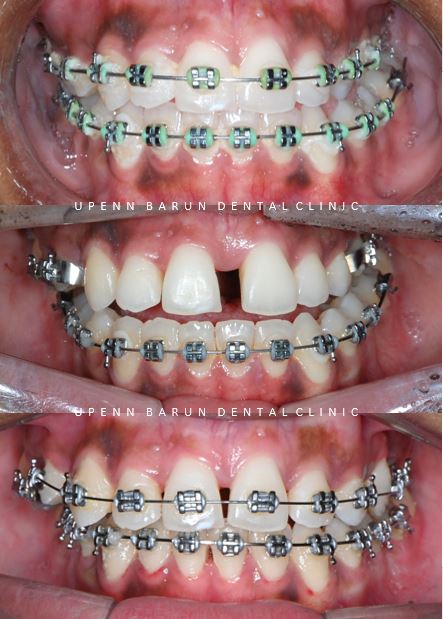

Case 2

두번째 소개해드릴 케이스는

3급 부정교합과 외상성 교합을 가진 환자분으로

아래 앞니가 깨져 있고

타치과에서

양악수술해야 한다는 소견을 듣고 오셨는데요,

반대교합이 있고

하악에 비해 상악의 악궁이 좁았을 뿐만 아니라

비수술적 치료를 원하셨기에

악궁확장장치로 상악 확장 후 인비절라인을 진행하기로 하셨습니다.

치료기간 23.3 ~ 23.5

'Marpe' 장치는 입천장 가운데를 중심으로 교정용 미니스크류가

양쪽의 앞, 뒤로 하나씩 4개 식립되어 있습니다.

앞니가 벌어진것 보이시나요?

악궁이 확장되며 생긴 공간으로 놀라지 않으셔도 됩니다 :)

이 공간을 활용해

인비절라인으로 나머지 치아를 재배열 하여

교정을 마무리 할 예정입니다.